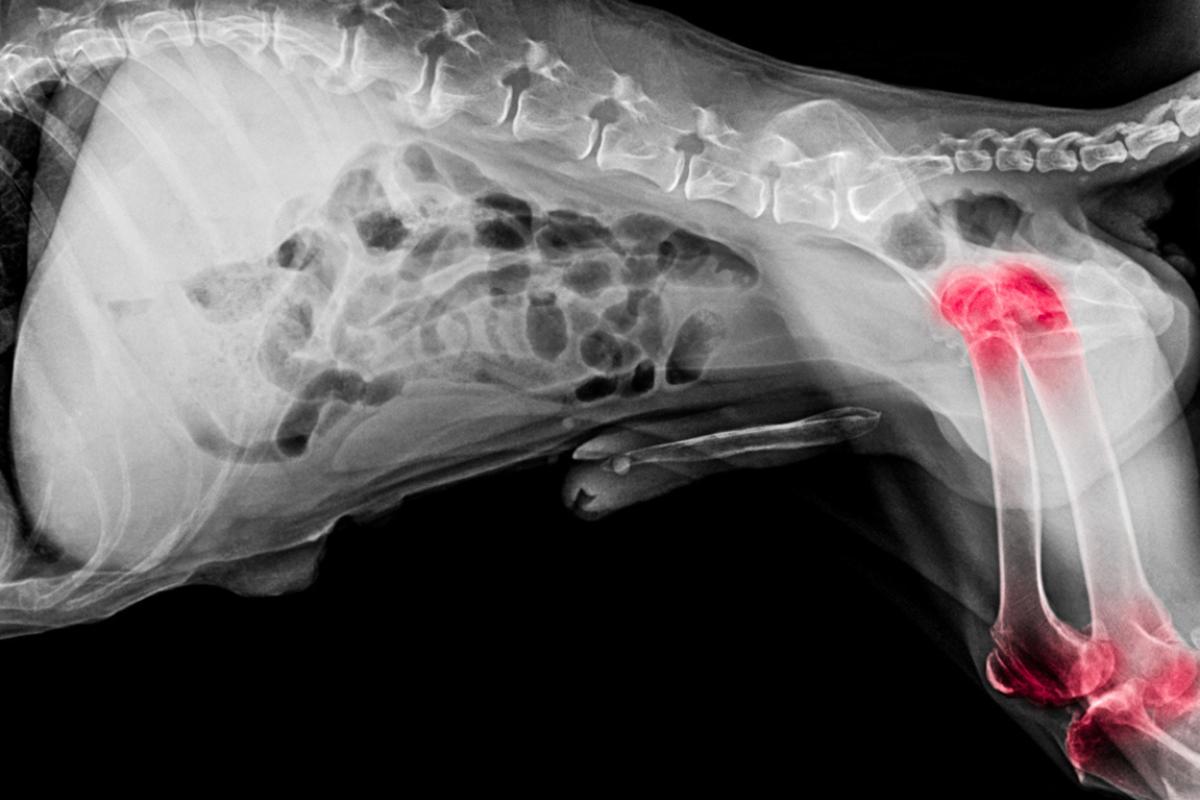

Generalmente, el harpagofito se emplea asociado a otros fármacos y nutracéuticos para tratar patologías articulares crónicas en el perro. En concreto, se utiliza para manejar el dolor y la inflamación articular asociados a las siguientes enfermedades:

- Osteoartritis (OA) o artrosis.

- Artritis reumatoide.

- Inflamaciones de los tejidos blandos articulares, como bursitis o tendinitis.

- Traumatismos articulares.